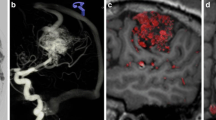

Ruptured thalamo-perforating branch micro-aneurysm. a Baseline magnetic resonance imaging (MRI) demonstrating a bithalamic hemorrhage. b No sign of central venous thrombosis. c Digital subtraction angiography (DSA) run of the posterior circulation in the lateral projection with normal findings. d Three-dimensional rotational angiography (3DRA) showing a small aneurysm (white arrow) in the course of a left thalamo-perforating branch. e,f 3DRA + MRI fusion clearly demonstrates the aneurysm located within the left thalamic hemorrhage as the bleeding source

The DSA demonstrated caliber irregularities of multiple intracranial vessels and no arteriovenous shunt. A 3DRA demonstrated a small aneurysm (2 mm) in the course of a left thalamo-perforating branch with vague contact to the thalamic hemorrhage. Fusion of the T2-SPACE and a 3DRA clearly demonstrated the aneurysm location within the left thalamic hemorrhage. Because of multiple diffusion restrictions in different vascular territories, vessel wall enhancement, and vessel wall irregularities of medium and small caliber arteries, even in the absence of cerebrospinal fluid biomarkers, vasculitis was considered the most likely diagnosis. Due to the small vessel caliber (0.3 mm), superselective catheterization of the thalamo-perforating artery was unsuccessful. The patient made a good recovery after intensive cortisone treatment. Follow-up imaging demonstrated resorption of the thalamic hemorrhage.